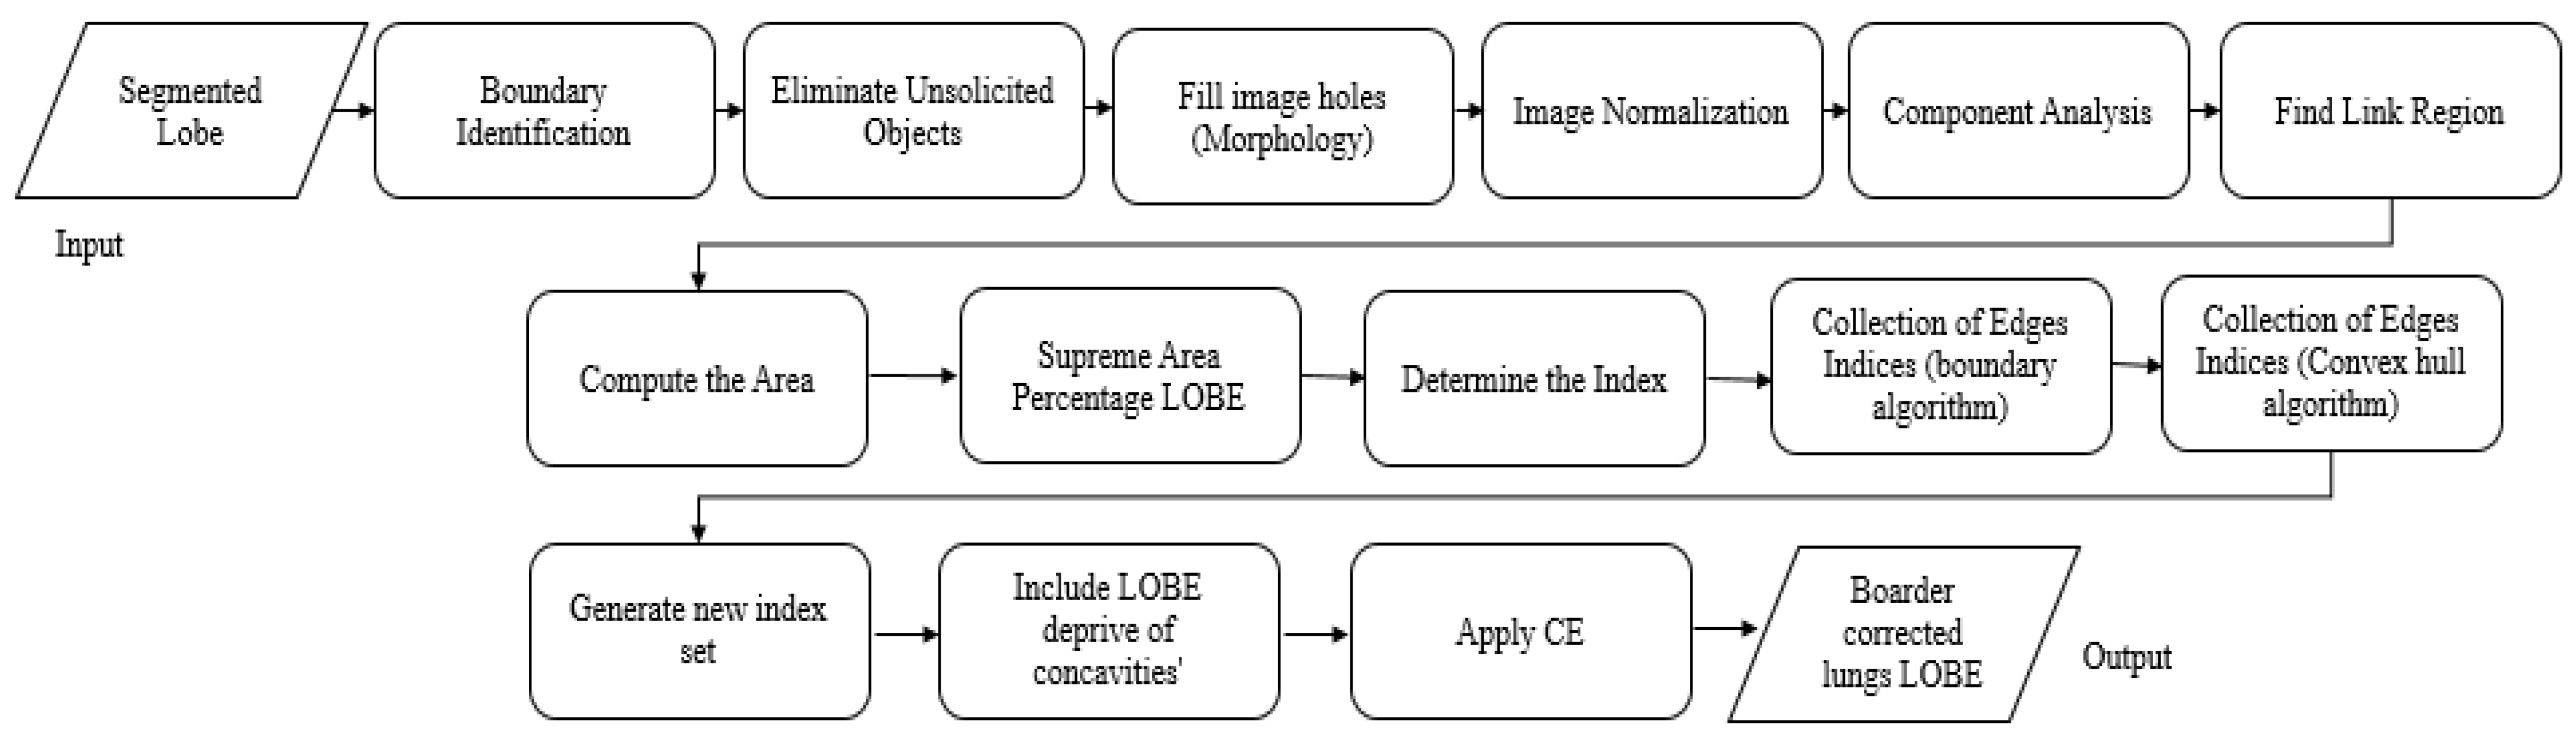

3.1.2. Novel Hybrid Border Concavity Closing (NHBCC) Algorithm

| Algorithm 2: NHBCC Algorithm |

| Input: ASSRG segmented lobe (right or left) (J), the width of the line (n) Output: Border-corrected lung lobe (Ibcl)

|